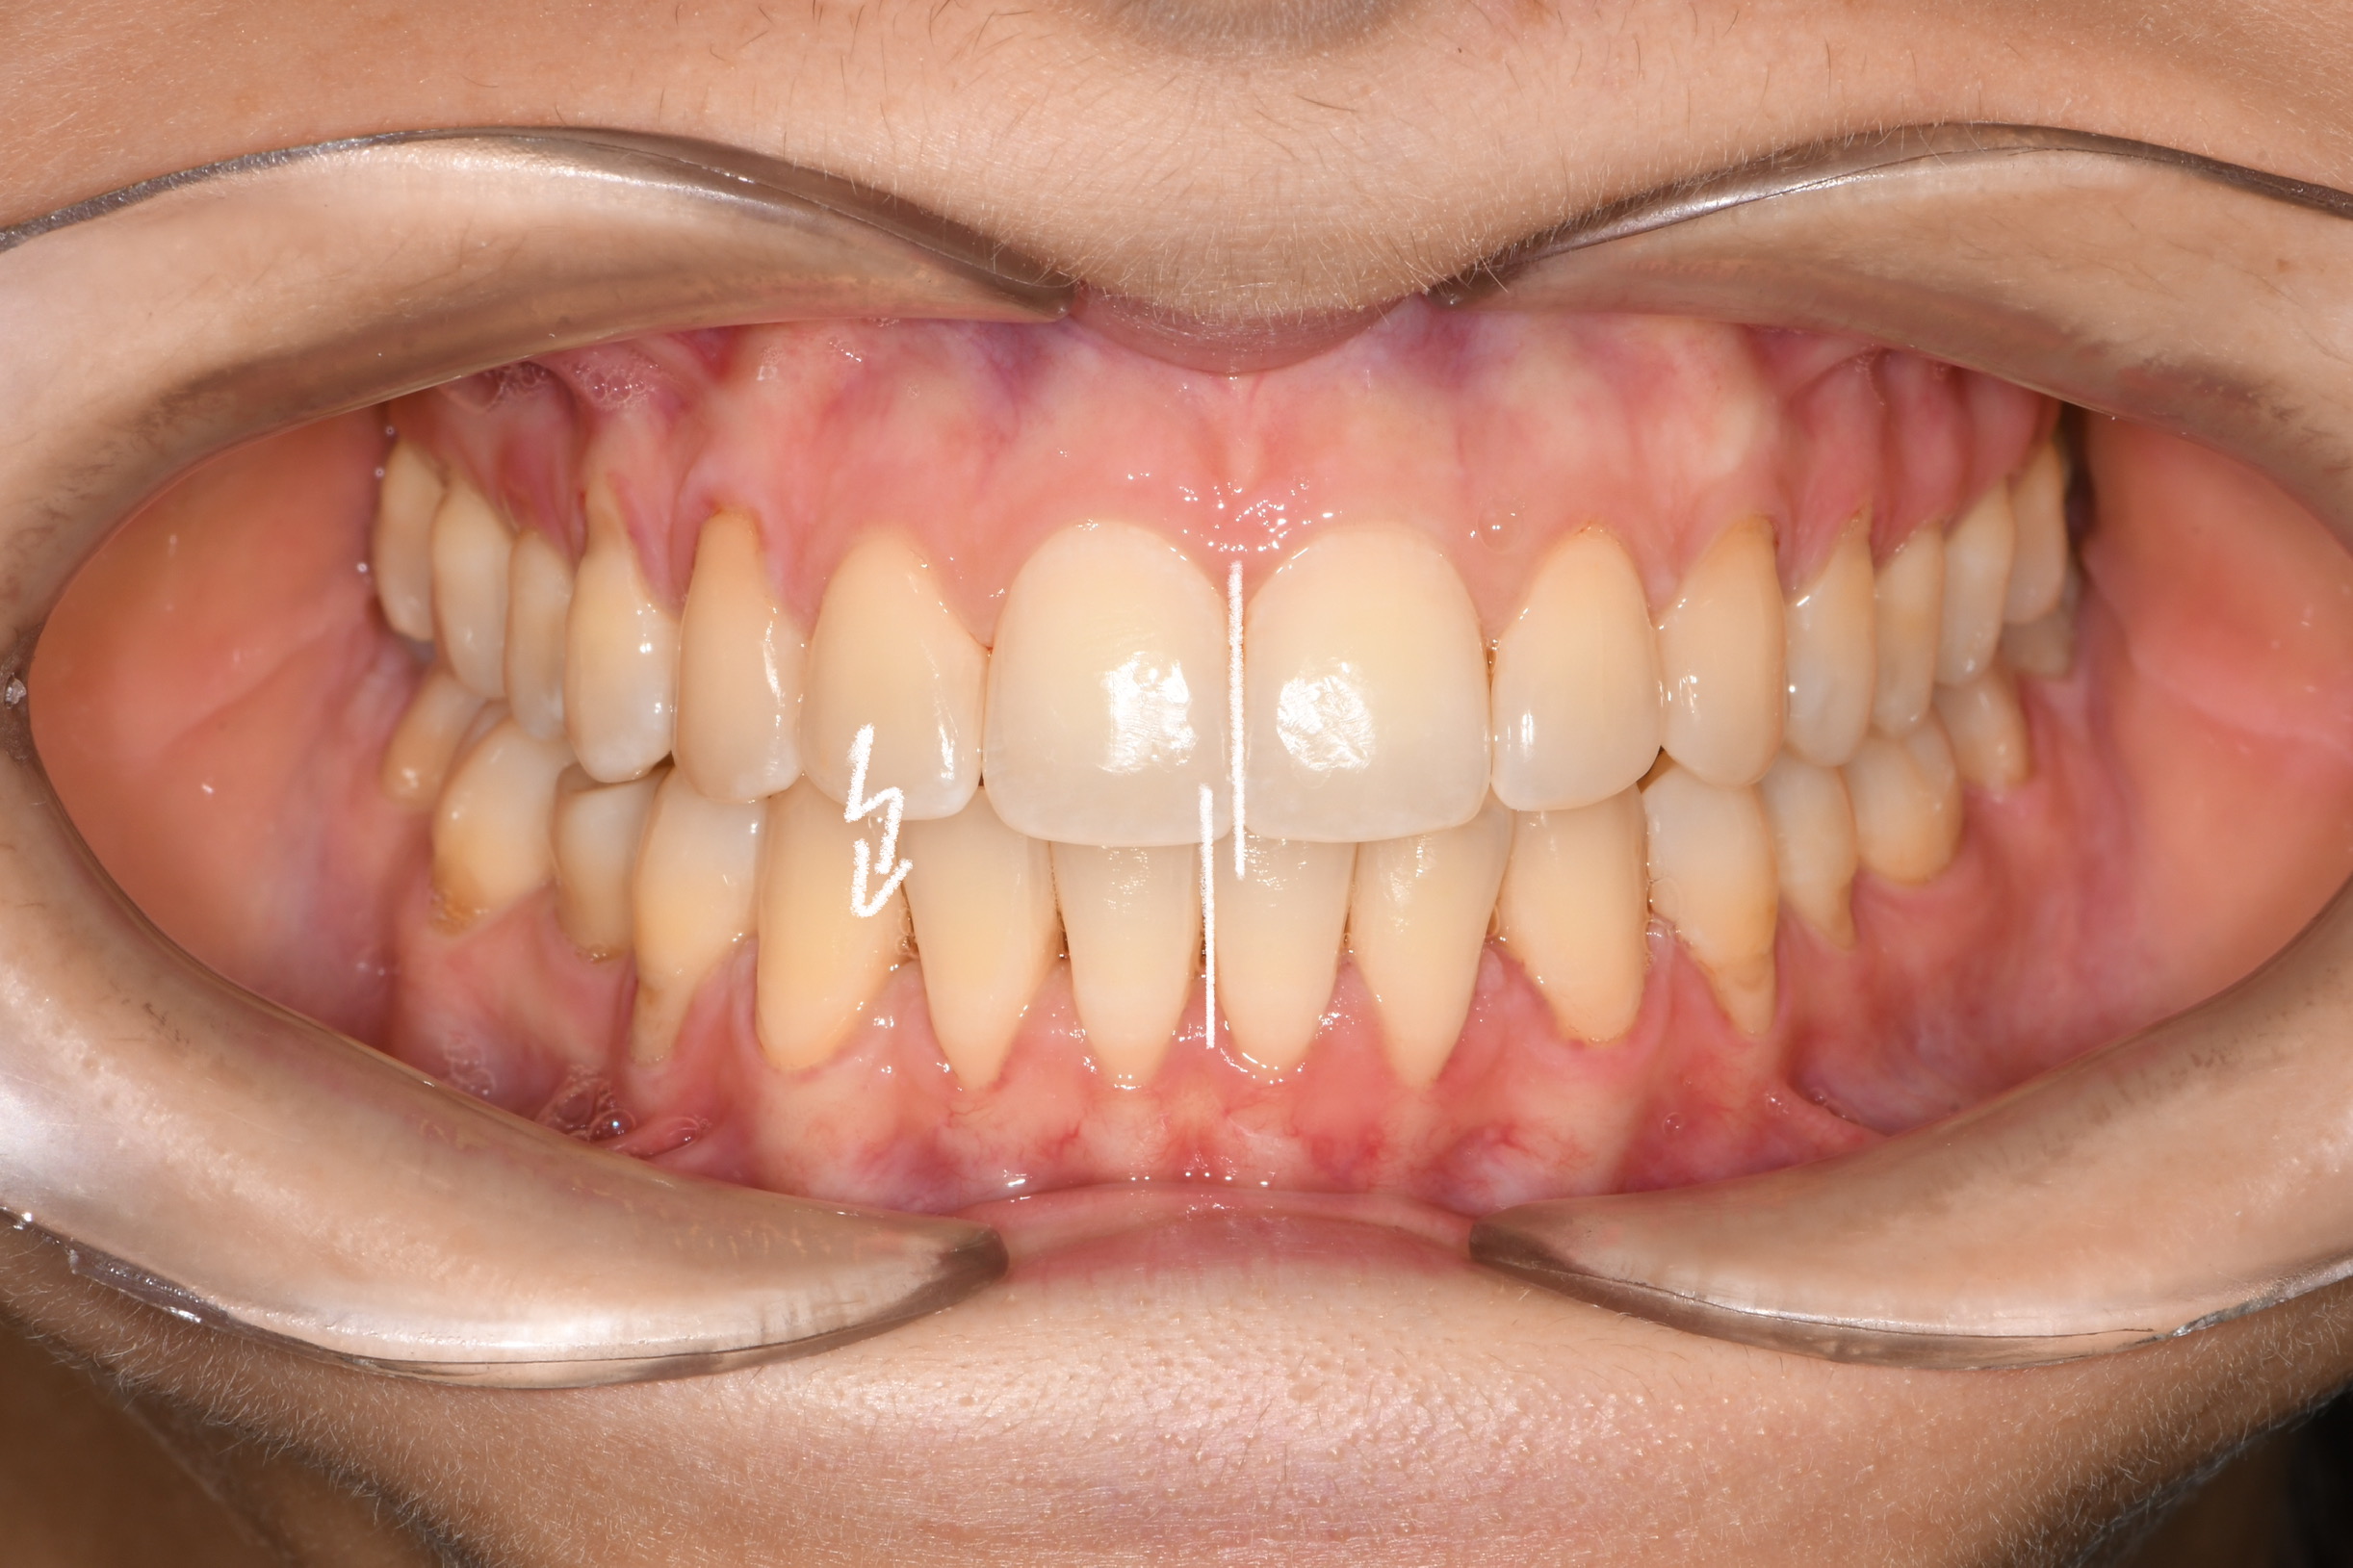

Az elmúlt évekből rengeteg szakmai referenciát tudnánk bemutatni, amelyek különböző fogszabályozási problémákat oldottak meg. Válogatva a több száz esetből, ezen az oldalon olyan képeket, információkat igyekeztünk bemutatni, amelyeknek a segítségével a jövőbeni pácienseinknek azt tudjuk üzenni: A Te fogsorod is lehet gyönyörű!

(Képeket a Pácienseink külön írásos beleegyezésével mutatjuk be!)